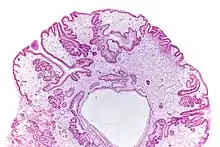

Micrograph of a gastric juvenile polyp, as may be seen in juvenile polyposis syndrome. H&E stain | |

Juvenile polyposis syndrome is an autosomal dominant genetic condition characterized by the appearance of multiple juvenile polyps in the gastrointestinal tract. Polyps are abnormal growths arising from a mucous membrane. These usually begin appearing before age 20, but the term juvenile refers to the type of polyp (i.e. benign hamartoma, as opposed to adenoma for example), not to the age of the affected person.[1] While the majority of the polyps found in juvenile polyposis syndrome are non-neoplastic, hamartomatous, self-limiting and benign, there is an increased risk of adenocarcinoma.